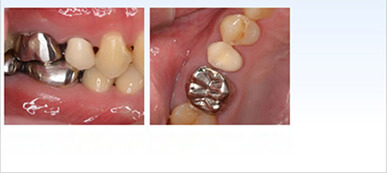

自家歯牙移植による歯の保存治療

この30歳代男性患者様は下顎左側第二大臼歯のかぶせ物の脱離を主訴に来院され、マイクロスコープによる診査・診断の結果、2本ある根の真ん中及び2本の根自体にもひび割れを確認、ひびからと思われる感染もあり長期的な予後は期待できないことを説明後、第二大臼歯の抜歯と同時に後ろにある健全な親知らずをドナーとした自家歯牙移植をご提案し患者様も同意されました。(この症例はかぶせ物以外保険治療で対応)

術前

術後